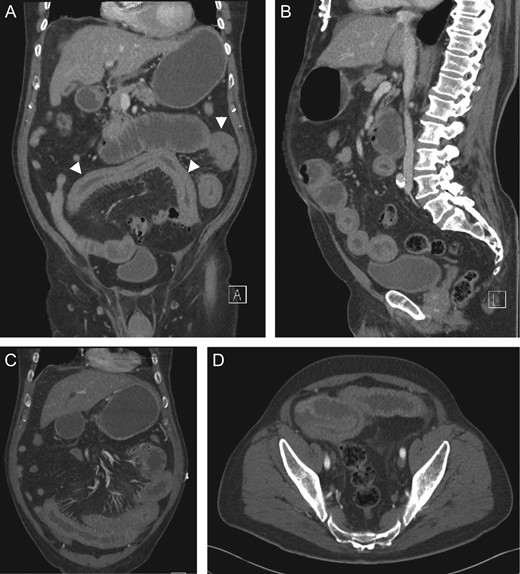

Coronal (A, C), sagittal (B) and axial (D) CT showing small bowel intramural haematoma up to the mid-ileum with associated oedema causing obstruction and proximal small bowel and gastric dilatation.

Non-contrast abdominal CT is the most valuable imaging modality. Diagnostic features include circumferential bowel wall thickening, intramural hyperdensity, luminal narrowing and intestinal obstruction [2]. Ultrasound is non-specific and may show intra-abdominal free fluid and intestinal wall thickening with an echogenic submucosa [2, 8].